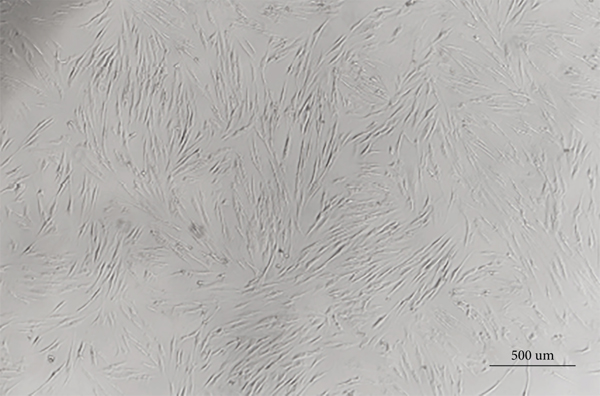

To identify the characteristics of hDPSCs, the morphology, immunophenotype, and multilineage differentiation potential analyses were performed. The morphology of primary hDPSCs presented a fibroblast- or spindle-like shape (Figure 1(a)). Flow cytometric analysis indicated that hDPSCs were stained positive for MSCs markers CD29, CD44, and CD105, but negative for leucocyte cell marker CD45 and platelet endothelial cell marker CD31 and CD34 (Figure 1(b)). Next, we performed a trilineage differentiation assay to confirm the pluripotency of hDPSCs. Extracellular calcium deposition was evaluated by ARS staining after 21 days of osteogenic induction. Evaluation of intracellular lipid accumulation was detected by oil red O staining after 21 days of adipogenic induction. Alcian blue staining exhibited positive glycosaminoglycan signal after 21 days (Figure 1(c)). All these data confirmed that hDPSCs were successfully isolated from the dental pulp.